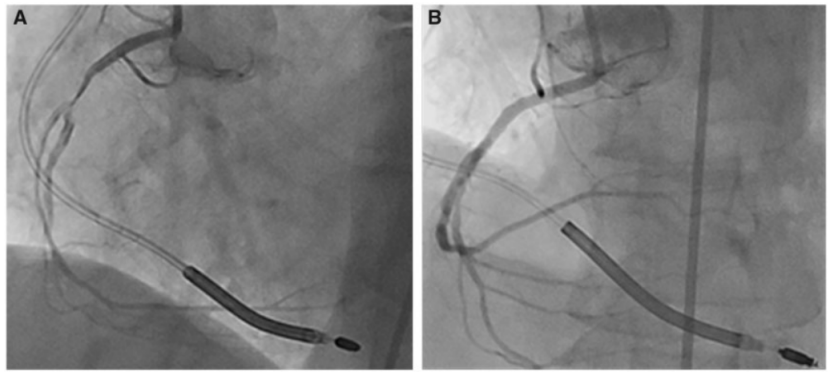

随着肌钙蛋白和肌酸激酶同工酶水平分别升高[分别为0.48 mg/L (正常0-0.02 mg/L)和35.7 mg/L (正常0-4.6 mg/L)], 考虑到患者有胸痛且伴有心血管危险因素 , 怀疑是不稳定型心绞痛或NSTEMI , 因此进行了冠状动脉造影 , 结果显示三支血管病变 , 右冠状动脉近端严重狭窄 , 直接给予植入支架 , 效果良好(图3) 。

文章插图

图3